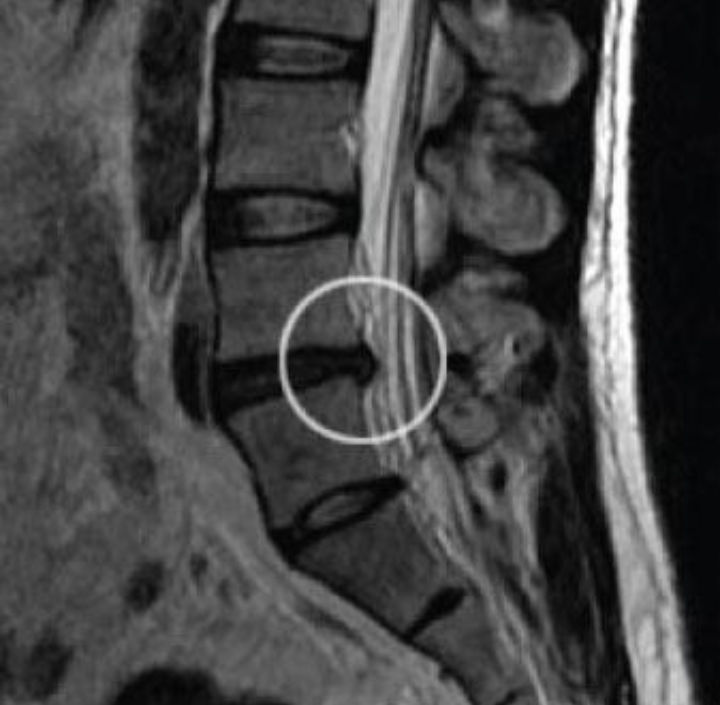

Plusieurs types de problèmes lombaires sont susceptibles d’être à l’origine d’ une cruralgie. Dans la majorité des cas la cause est une hernie discale, mais la cruralgie peut aussi être déclenchée par une discopathie ou dégénérescence du disque et par la formation d’ostéophytes ou “becs de perroquet” sur les vertèbres (arthrose). La cruralgie peut aussi survenir en cas d’accidents ou traumatismes qui touchent ce nerf.

La cause principale de l’inflammation du nerf crural est donc la hernie discale. Traiter les causes de la cruralgie revient donc à traiter les causes de la hernie discale.

La hernie discale survient lorsque les cellules du disque intervertébral vieillissent, se déssèchent, et ne sont plus régénérées et remplacées par des nouvelles cellules. Les tissus périphériques du disque perdent alors leur capacité à contenir le noyau du disque.